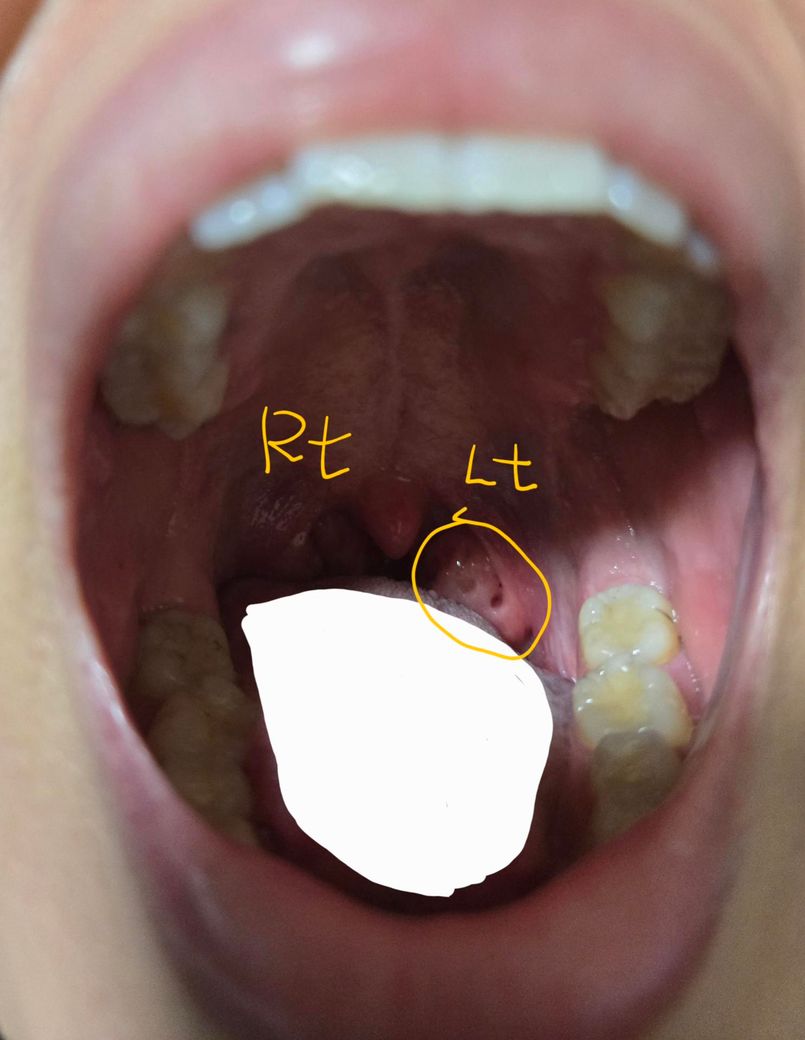

• 1번 째 사진

현재 사진에서는 왼쪽 편도에 구멍이 있는 것으로 보입니다. 보통, 편도 소립이라고 불리우는 구멍인데 해부학적으로 구조가 달라서 한쪽에만 결석이 생기는 경우가 간혹 발생하기도 합니다. (따라서 원래 한쪽만 그렇다고 보기는 어렵습니다.)